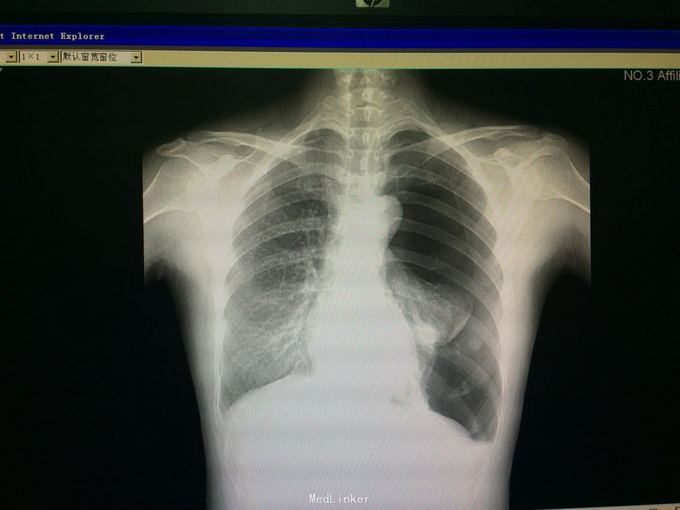

48岁女性,既往高血压。 主诉:咳嗽伴胸痛1周,气促3天。 现病史:1周前无明显诱因出现咳嗽,伴左侧胸壁刺痛,为持续性,活动时加重,休息时缓解。3天前出现气促,一般体力活动后出现,至我院查胸片示:左肺气胸,肺组织压缩约80%,遂入院。

诊断:左侧气胸,高血压1级、中危。 入院后予胸腔穿刺加闭式引流排气术,并予头孢咗肟预防感染治疗。负压引流瓶未及气泡冒出、听诊左肺呼吸音明显增强后予夹管复查胸片,示左肺气胸较前好转。